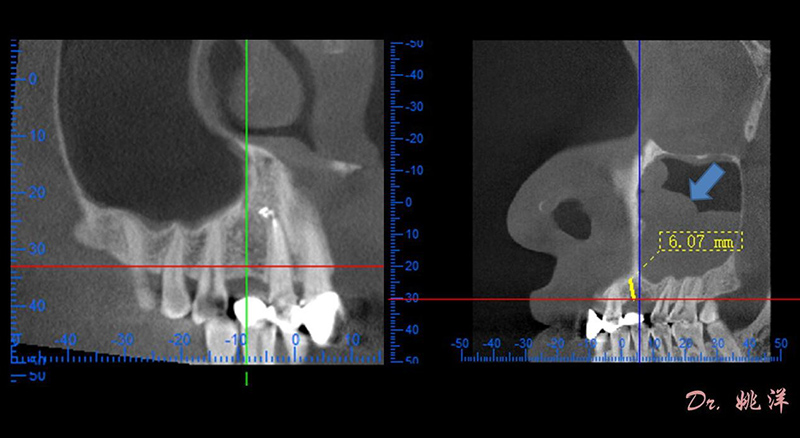

觀察患者CT,可看出患者有上頜竇粘膜囊腫,粘膜囊腫為竇內(nèi)腺體阻塞所致,視情況可有手術(shù)摘除和不予處理兩種方法,此次患者拒絕手術(shù)摘除,故需規(guī)避上頜竇位置。

根據(jù)患者CT顯示,使用種植導(dǎo)航軟件設(shè)術(shù)前手術(shù)方案??紤]到患者拒絕手術(shù)摘除上頜竇囊腫等因素,此次手術(shù)選用了Straumann骨水平4.10*8.0mm的植體,植體末端位點設(shè)計距上頜竇底壁2mm處的同時兼顧種植方向和修復(fù)間隙,來達(dá)到理想的效果。

從術(shù)后CBCT顯示可以看出,手術(shù)操作中完美地避開上頜竇底,并兼顧了正確的種植方向和修復(fù)間隙